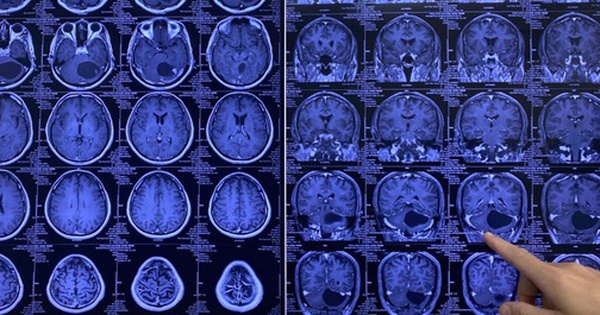

150 phút nghẹt thở với người đàn ông vào bệnh viện trong tình trạng đau đầu dữ dội

Với u não, một sơ suất nhỏ có thể gây chảy máu ồ ạt, dẫn đến di chứng liệt toàn thân hoặc tử vong ngay trên bàn mổ.